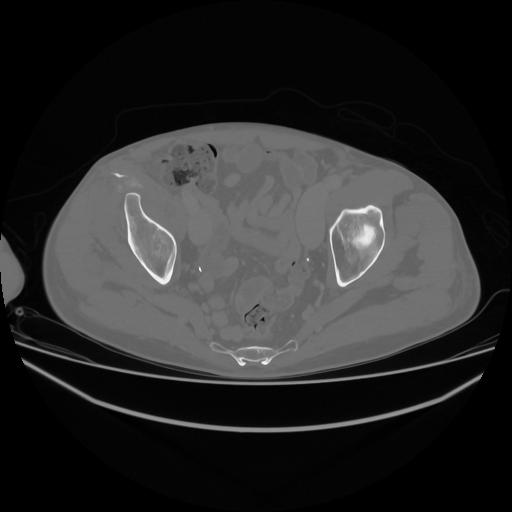

5 CUERPO,CE,Vol,1.0,CUERPO,,